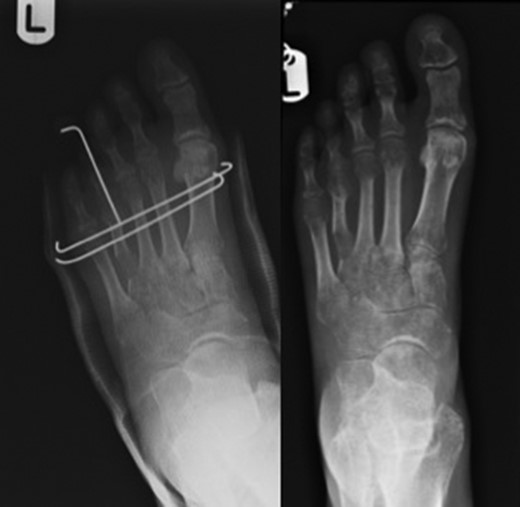

The majority of publications regarding gradual bone lengthening describe the use of unilateral external fixators with scant publications on the use of semi-circular external fixators [9] and none reporting the use of circular external fixators (Fig. 2).

Figure on the left showing trans-metatarsal K-wires in-situ along with the toe carrying wire cut and left alone. Figure on the right showing callus formation over distraction zone.

The aim of this prospective case series is to assess outcomes and complications of a novel technique for gradual metatarsal lengthening using a circular fixator followed by trans-metatarsal k-wire fixation. The circular external fixator applies Ilizarov principles which describes the importance of increased frame stability and thus better control of alignment and reduced subluxation [5]. The trans-metatarsal k-wires (Fig. 3), placed after removal of the external fixator, prevents further subluxation. We theorise that using a circular external fixator followed by trans-fixation metatarsal k-wires could reduce complication rates associated with distraction osteogenesis using external fixators and potentially improve the healing time along with restoration of metatarsal parabola and subsequently improving the biomechanics of the forefoot (Fig. 4).

Pre-operative image on the left with image on the right showing successful lengthening.